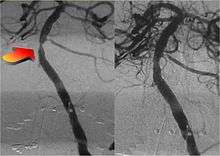

The technique that constitutes the basis for angiographic neurointerventions, and thus, interventional neuroradiology, was first developed in 1927 by the Portuguese physician Egas Moniz at the University of Lisbon to provide contrasted x-ray angiography in order to diagnose several kinds of nervous diseases, such as tumors, coronary heart disease and arteriovenous malformations. He is usually recognized as one of the pioneers in this field. Moniz performed the first cerebral angiogram in Lisbon in 1927.